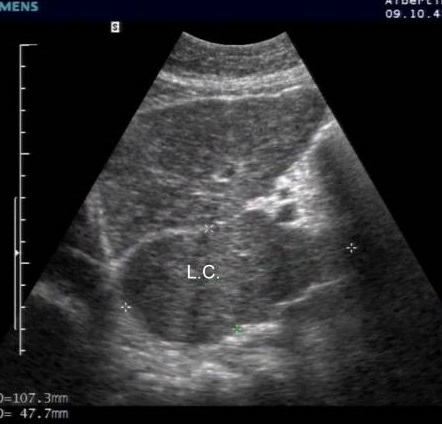

Aspect

echographique de la cirrhose du foie : Foie gauche est

heterogen . a bord irreguliaire ,angle est obtus .

Lobe caude est hypertrophie a inferieure , et hypoechogene |